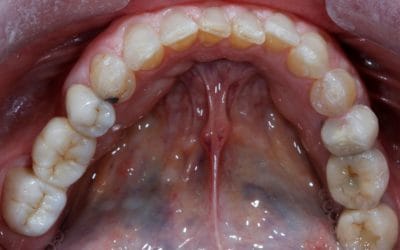

Rehabilitación Oclusal posterior + Rehabilitación estética anterior. ( Superior )

Paciente que presentaba ausencia de los dos sectores posteriores de la arcada superior. Al carecer de volumen oseo, se realizó unas elevaciones de seno bilaterales con las que regenerar suficiente volumen óseo.

A continuación se procedió a colocar 5 implantes, y sobre los mismos dos puentes atornillados a ellos.

En la zona anterior, se procedió a cambiar unas coronas antiguas sobre los incisivos centrales. Previamente se realizó un alargamiento coronado para establecer un equilibrio en el tamaño de los dientes. Posteriormente, se tallaron los dientes y se cementaron sobre los mismos, coronas cerámicas de Zirconio con carillas cerámicas con las que caracterizar el caso.